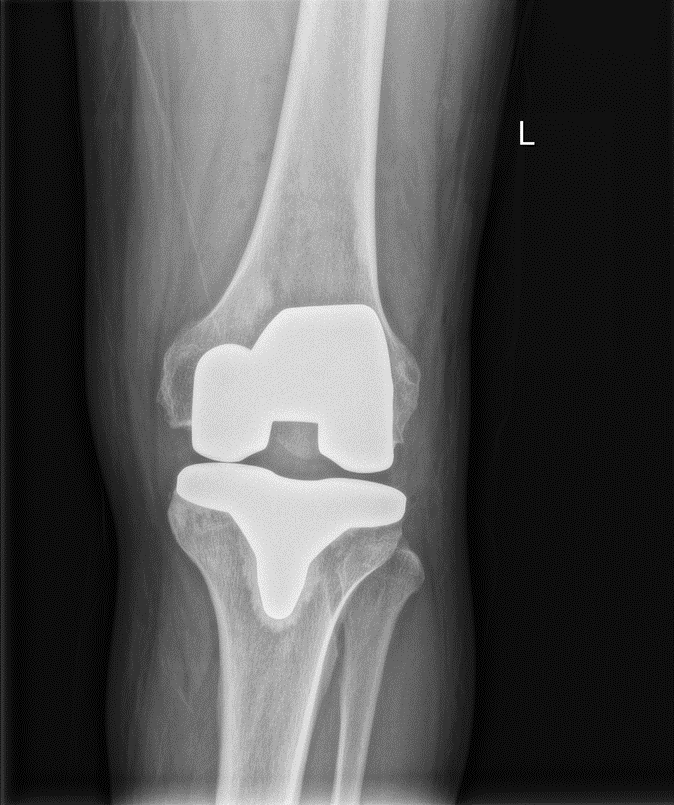

膝关节OA 左侧膝关节全膝置换术(TKA)

术后2日 引流管拔除后开始功能锻炼。后7天屈曲超过90°,6周后步行不需要辅助。 目前人工膝关节可供选择的假体很多,各位同道是如何取舍的呢?